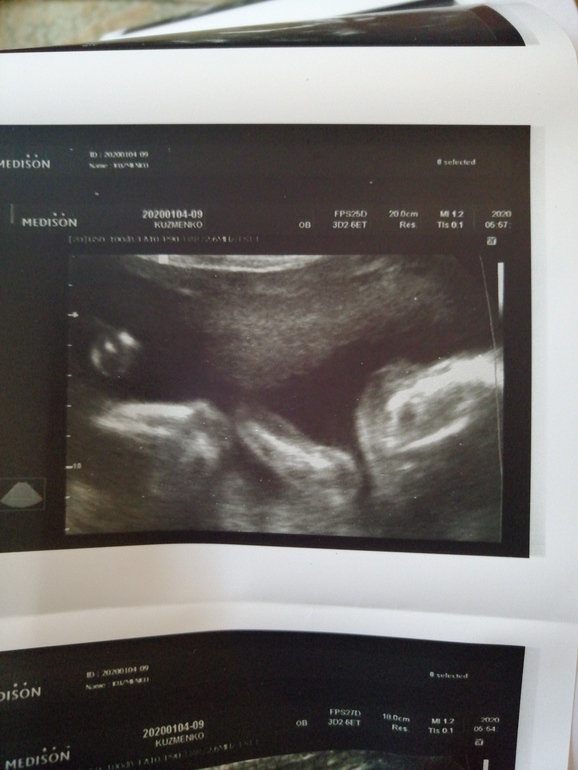

Мой внеплановый поход на узи (фото)

УЗИ, КТГ, доплерВрачи говорила контролировать тяж и ходить переодически на узи , сегодня как раз и решила сходить))) Аришка заметно подросла, догнали по срокам, ранее опаздывала на недельку почти, весит мой пузяш маленький уже 470 грамм, а самое радостное и важное ПРОПАЛ ЭТОТ АМНИОТИЧЕСКИЙ ТЯЖ🤗🤗🤗🎉🎉🎉🎉🥳🥳🥳🌼 Я довольна и спокойна😍🥰😊Ну и фоточки моей бубочки, 22 недели и 3 дня